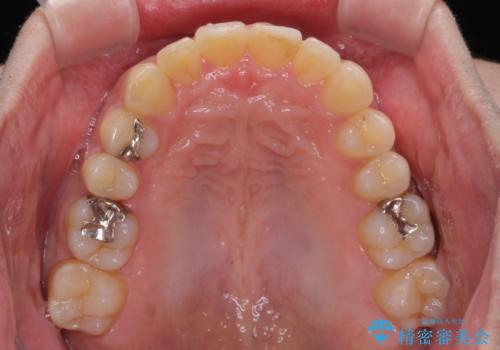

深い咬み合わせで顎が疲れる ワイヤー矯正でディープバイトを解消

歯ぎしりができないくらい強い食いしばりの咬合状態であったため、奥歯の歯軸を起き上がらせることで咬合を挙上させ、歯ぎしりができるようにしていくこととしました。

下顎が左側にずれているため、上下正中は最大限合わせられるところまで合わせるゴールとなりました。